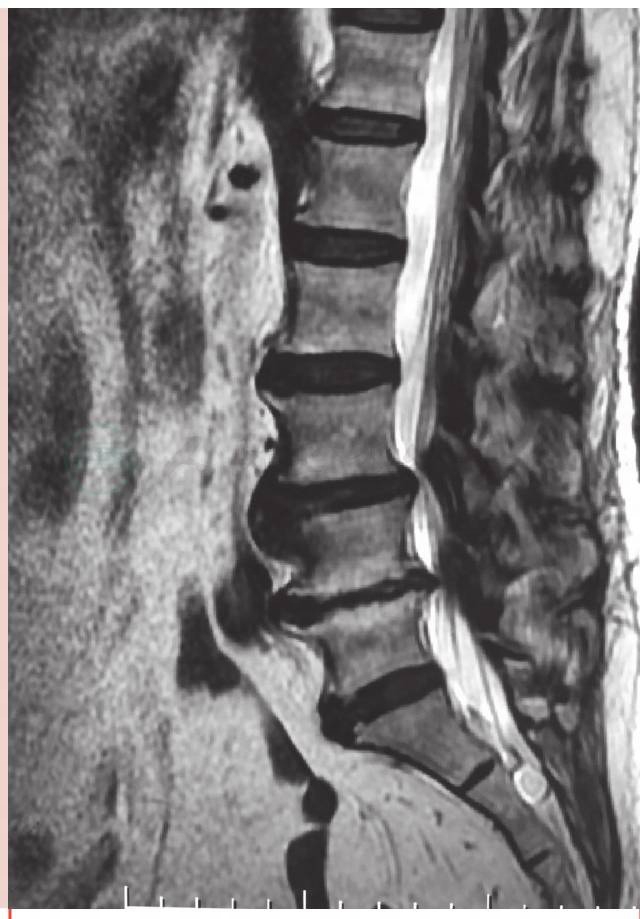

术前磁共振(MRI)示:腰椎退行性变,L3-4、L4-5、L5-S1椎间盘膨出及突出,L4、L5椎体终板炎(图1)。

图1 术前磁共振(MRI)示 L3-S1椎间盘膨出及突出,L4、L5椎体终板炎